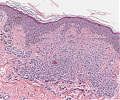

A63 Basaliom

Basaloide Tumorformationen mit palisadenartiger Begrenzung der Zellnester.

-

A63 Basaliom

Tumorinfiltration, ausgehend von der Epidermis

Basaliom_A63.png

Erkennbar sind Tumorzellnester mit pallisadenförmiger Anordnung der Tumorzellem am Rand